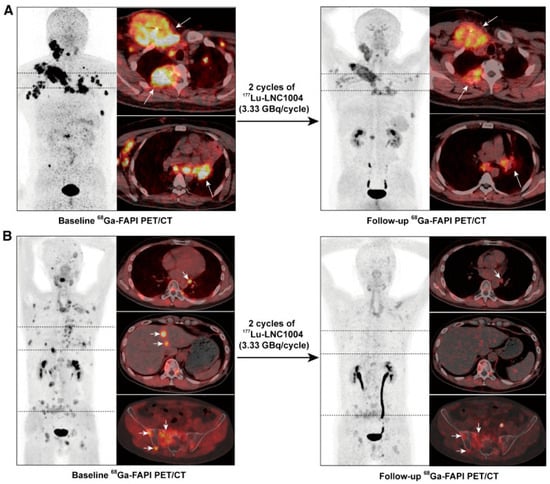

- Fu, H.; Huang, J.; Zhao, L.; Chen, Y.; Xu, W.; Cai, J.; Yu, L.; Pang, Y.; Guo, W.; Su, B.; et al. 177Lu-LNC1004 Radioligand Therapy in Patients with End-Stage Metastatic Cancers: A Single-Center, Single-Arm, Phase II Study. Clin. Cancer Res. 2025, 31, 1415. [Google Scholar] [CrossRef] [PubMed]

| Fu et al. (2023) [19] | 6 weeks after second cycle | 2 | Bone metastases: 5.12 Metastatic lymph nodes: 5.95 Other metastases: 15.27 Kidneys: 1.32 Bone marrow: 0.11 | NR | PR: 3/12 (25%) SD: 7/12 (58%) PD: 2/12 (17%) | NR | NR |

| Fu et al. (2025) [47] | 18.1 months | 2 | Primary tumor lesions: 4.69 Bone metastases: 4.57 Metastatic lymph nodes: 4.88 Lung metastases: 6.47 Other metastases: 3.77 | NR | PR: 4/20 (20%) 2 SD: 9/20 (45%) 2 PD: 7/20 (35%) 2 | NR | 4 (6.3) |

| [177Lu]Lu-EB-FAPI | Albumin-binding small molecule | Prolonged tumor uptake up to 7 days in the dose-escalation study and up to ≈2 weeks in the expanded cohort; longer effective half-life in bone metastases than in lymph nodes and other lesions. Effective blood half-life (0.21 ± 0.11 h, half-life α; 68.01 ± 26.69 half-life β). | Primary lesions: 4.69 ± 3.83; bone metastasis: 4.57 ± 1.98; lymph node metastasis: 4.88 ± 4.39; lung metastases: 6.47 ± 6.75; other metastases: 3.77 ± 1.74. | Fu et al. [47] Wang et al., 2025 [60] |